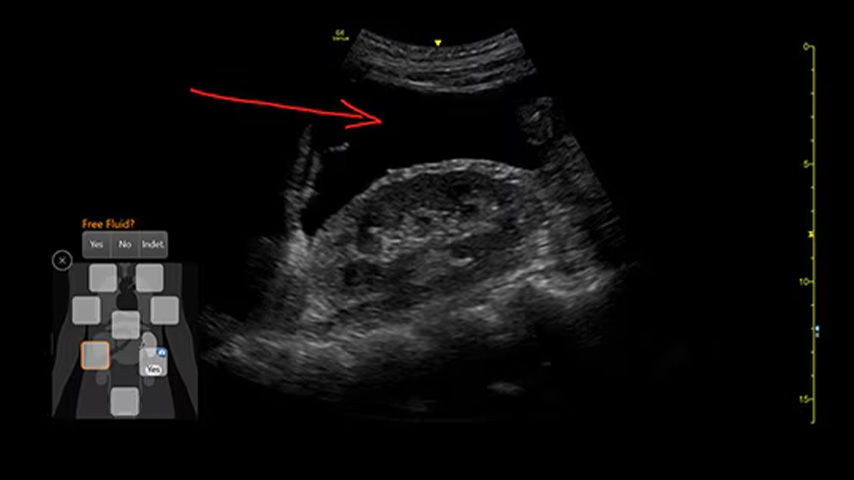

Quickly assess patient status in trauma cases with eFAST Tool

Allows users to map key areas of the body in a structural way that is intuitive and aligned with clinical workflows. Also saves keystrokes and helps provide consistent reports from user to user.

Take a structured approach to patient assessment with eFAST tool

Users can easily assess patient status with this tool that simplifies scanning order, documentation, image storage and review.

• Scan different zones sequentially, in a predetermined order, or in any order you desire.

• Document findings with single keystrokes and touch screen controls.

• Store images by using a visual anatomical diagram, with next step recommendations provided.

• Label each zone with the relevant finding while scanning.

• View a summary during or after the exam, showing the stored images superimposed over the anatomical diagram.